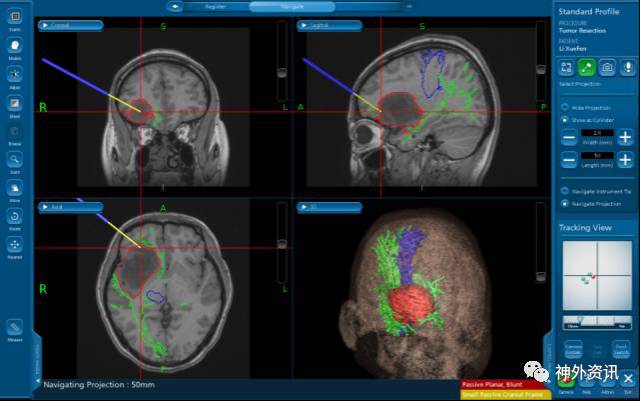

手术导航